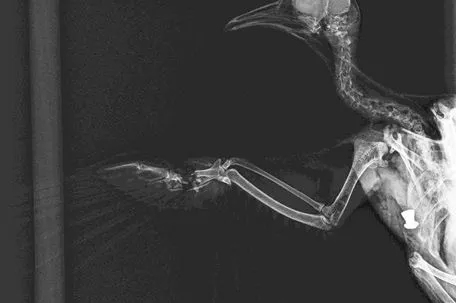

Am Montagnachmittag wurde eine verletzte Türkentaube aus der Stadt Salzburg zum Tierschutzhof Pfotenhilfe in der Grenzregion Oberösterreich/Salzburg gebracht. Eigentlich ein Routinevorgang, da die dortige Wildtierstation jährlich hunderte verletzte und verwaiste Wildtiere versorgt, gesundpflegt und wieder auswildert. Doch die Taube hatte neben einer schweren Flügelverletzung auch ein großes rundes Loch in der Brust, das gleich als Einschussloch erkannt wurde, woraufhin das Tier direkt in die Tierklinik gebracht wurde. Noch am selben Abend kam dann die traurige Nachricht samt Bildern, dass die Taube so schwere Schussverletzungen hatte, dass sie nur noch erlöst werden konnte. Man erkennt auf dem Röntgenbild sogar deutlich eine Luftdruckgewehrpatrone.